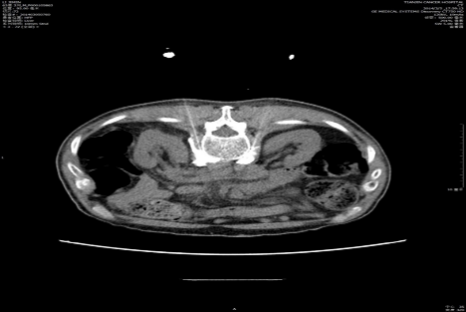

案例5:

患者女性,60岁,诊断为右肺癌胸壁转移,右侧胸壁持续性疼痛1周,NRS评分7分,既往未应用阿片类药物。PCA方案及治疗经过:①给予吗啡PCSA给药,参数设置如下:负荷剂量为0,背景剂量为0,Bolus剂量=5 mg,锁定时间=20 min,每小时最大剂量=15 mg;24h内患者按压PCA 4次,有效按压4次,疼痛NRS评分2-3分,无不良反应。②第二天,计算前24h PCA吗啡总剂量为5 mg×4=20 mg,换算为口服吗啡MED为20 mg×3=60 mg,则给予口服吗啡缓释片30 mg q12h,PCA单次按压有效剂量不变;③ 第3天,评估患者前24h按压PCA 1次,有效1次,疼痛NRS评分 1-2分,无不良反应;因24h按压1次,有效,滴定结束,停用PCA,继续口服吗啡缓释片剂量30 mg q12h,同时备用速效吗啡片10 mg/次处理爆发痛。